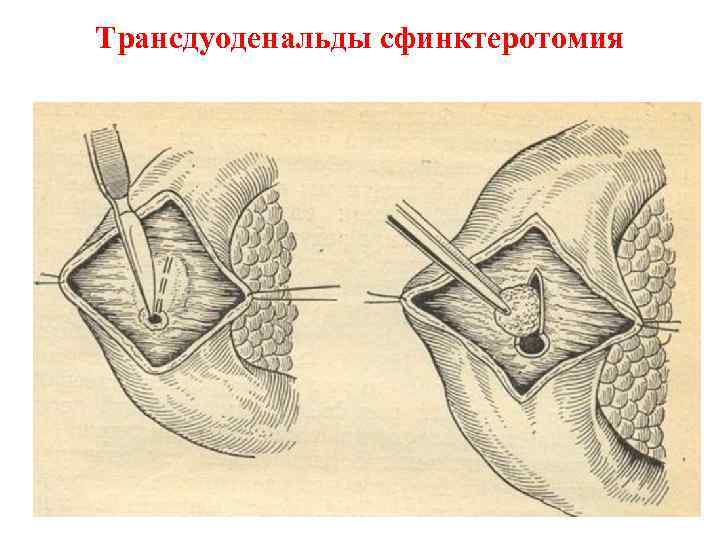

Трансдуоденальды сфинктеротомия